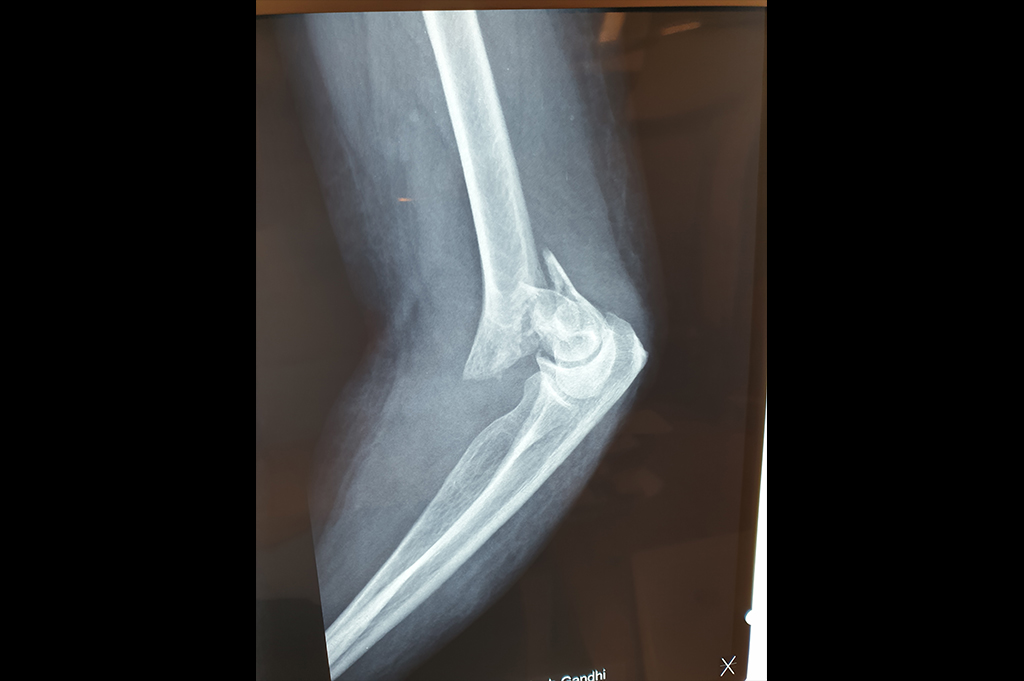

Elbow